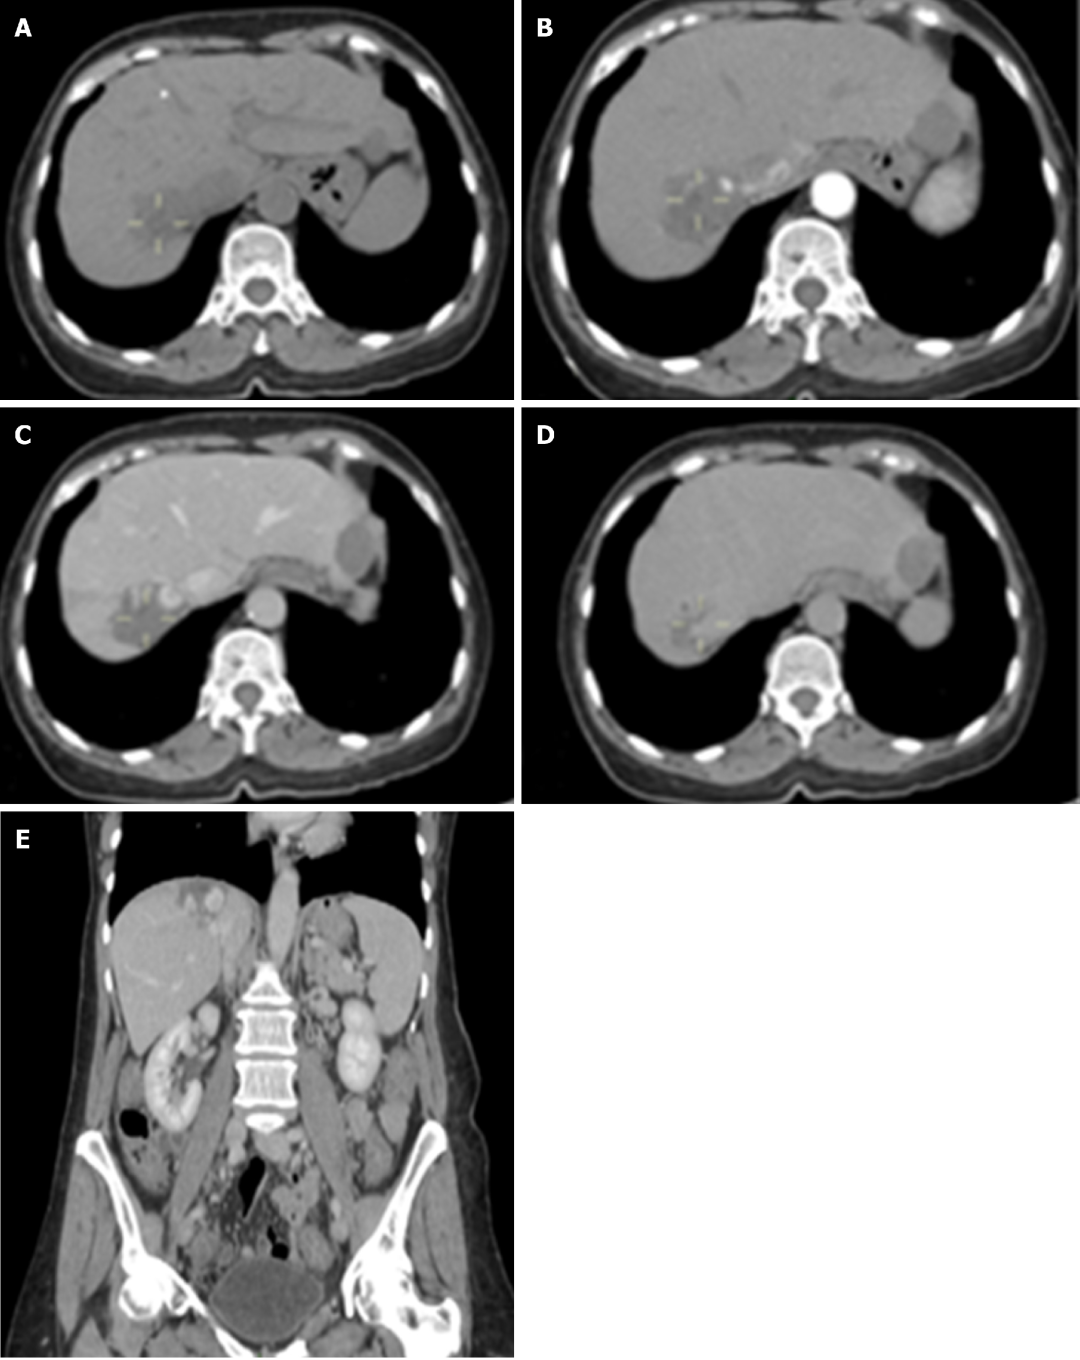

图2 CT检查

分型:根据肿瘤数目和直径,HH可分为3型:Ⅰ型:肿瘤数目1个,肿瘤直径<5 cm(Ⅰa型),肿瘤直径为5-10 cm(Ⅰb型),肿瘤直径>10 cm(Ⅰc型);Ⅱ型:肿瘤数目2-5个,肿瘤直径或直径之和<10 cm(Ⅱa型),肿瘤直径或直径之和为10-20 cm(Ⅱb型),肿瘤直径或直径之和>20 cm(Ⅱc型);Ⅲ型:肿瘤数目>5个,弥漫,肿瘤体积≤50%肝体积(Ⅲa型),肿瘤体积>50%肝体积(Ⅲb型)。